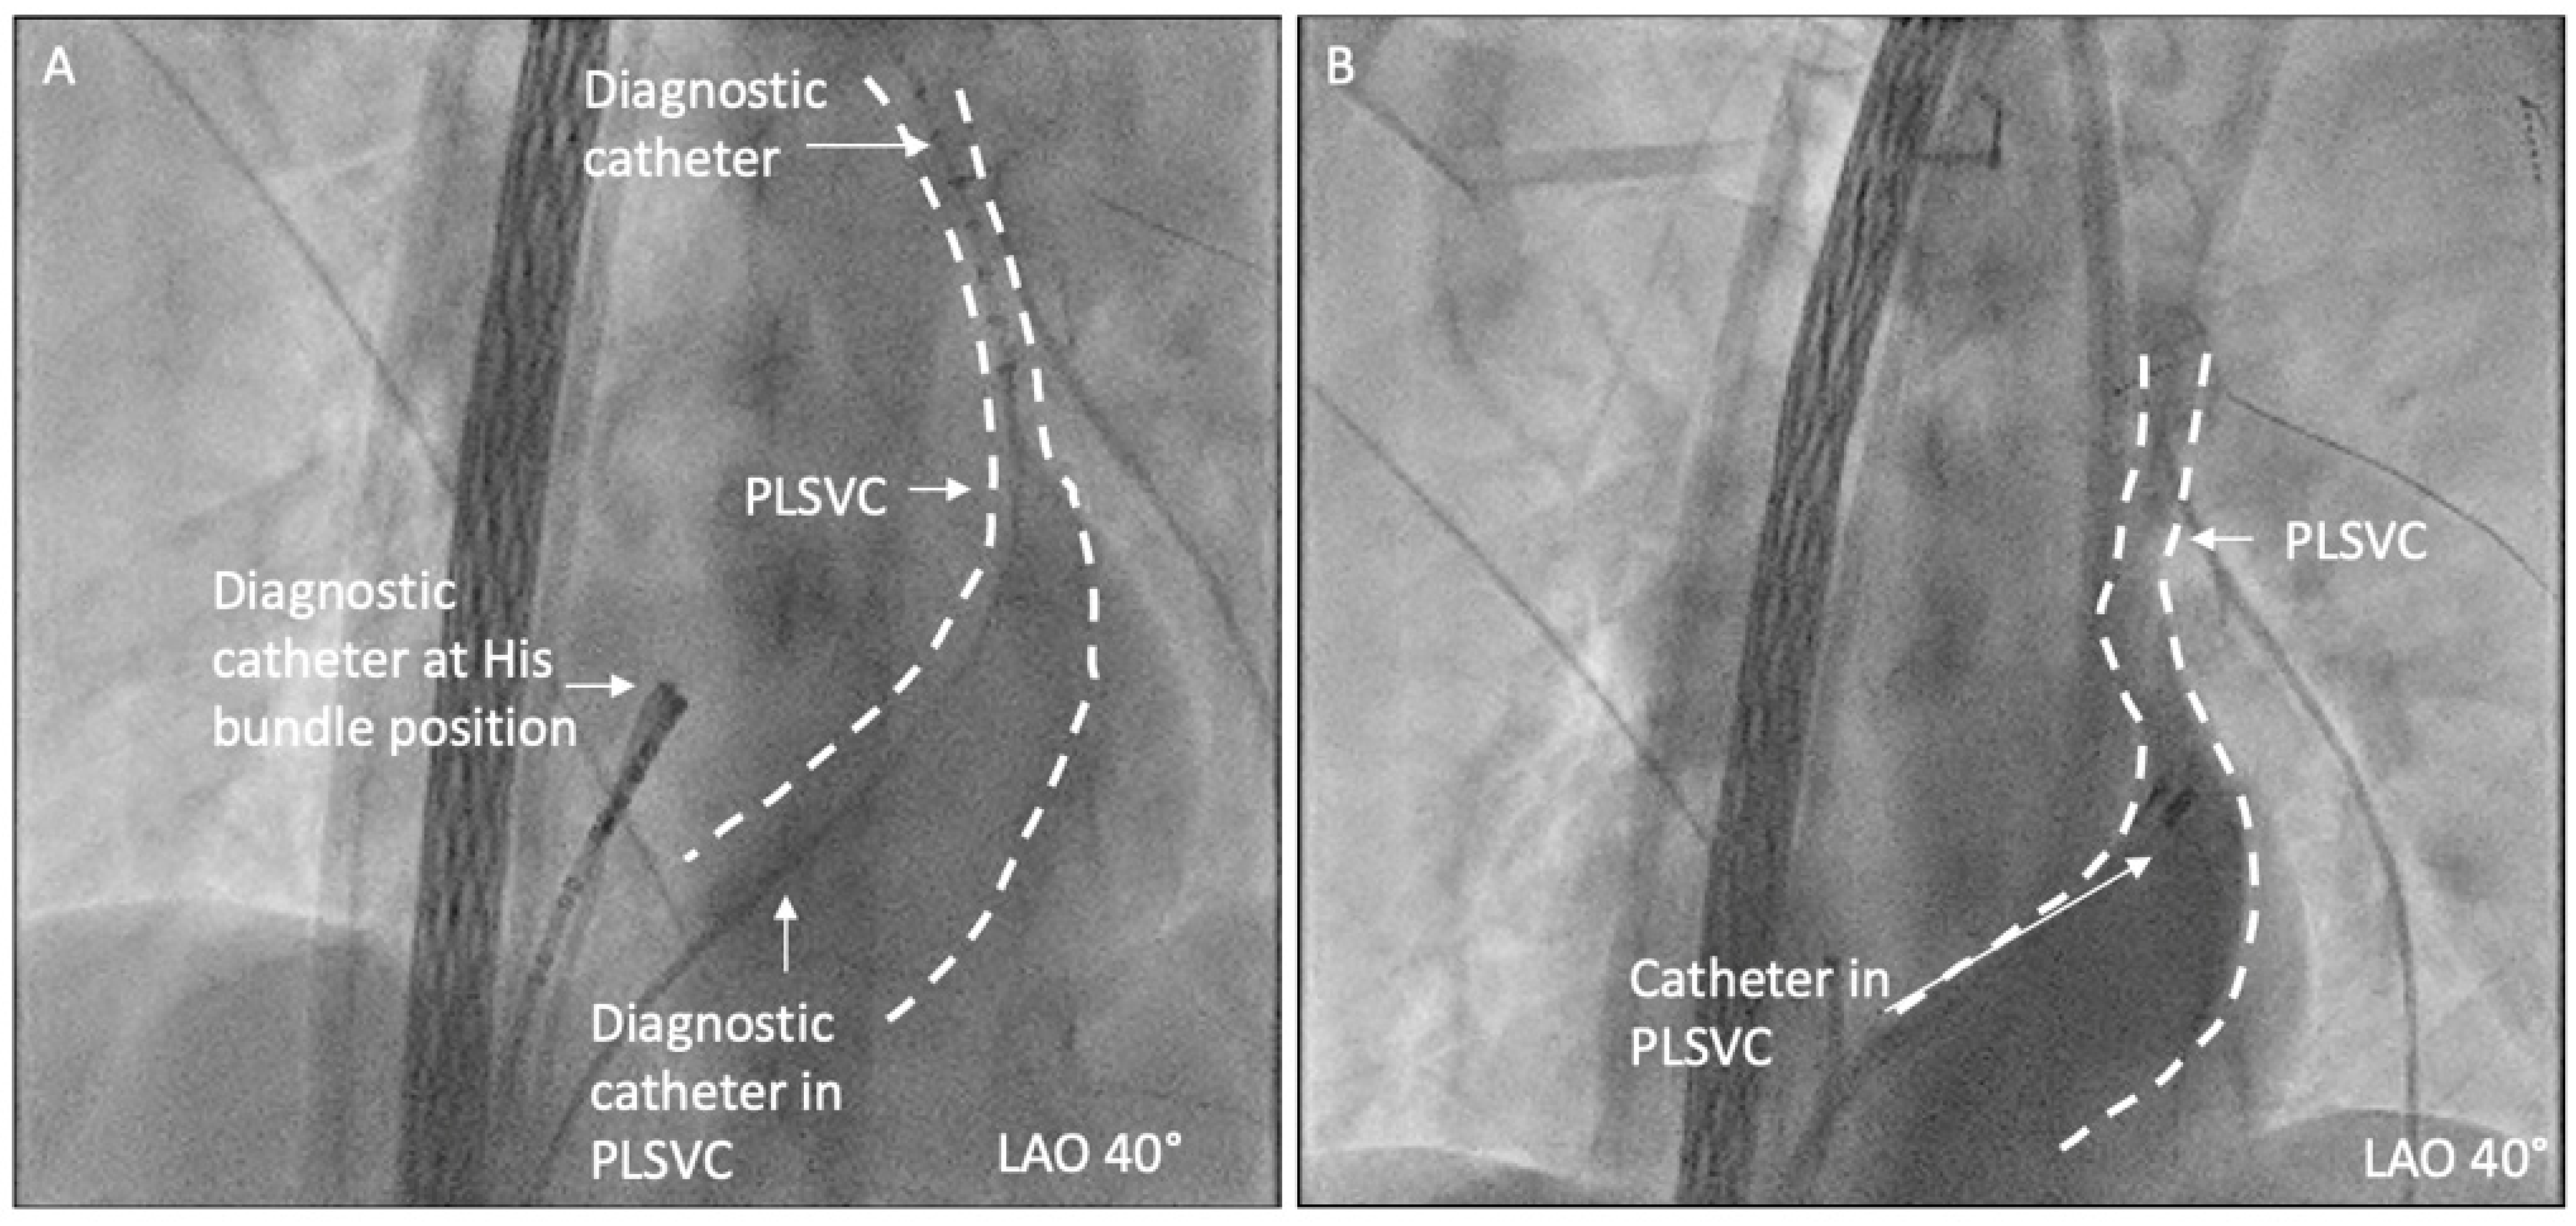

2.3. Ablation Strategy

2.4. Outcome